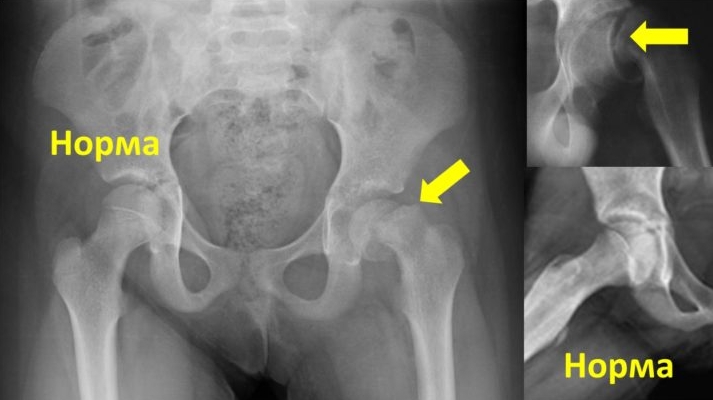

Для окончательной диагностики эпифизеолиза применяются инструментальные методы, такие как рентгенография и магнитно-резонансная томография. На рентгеновских снимках в двух проекциях можно заметить размытые границы эпифиза и увеличение ростковой хрящевой ткани. В области метафиза, рядом с эпифизарной пластинкой, отсутствует характерный сетчатый рисунок в зоне роста. Костная структура головки бедра остается неизменной, тогда как шейка приобретает слоисто-пятнистый вид.

В более запущенных случаях могут наблюдаться следующие изменения:

- выпрямление верхнего контура шейки бедра, имеющего полуовальную форму;

- уменьшение высоты эпифиза;

- утолщение и укорочение шейки бедра с образованием шипа.

При прогрессировании заболевания эпифиз смещается назад, под ним формируется «шпора», а суставная щель начинает сужаться.